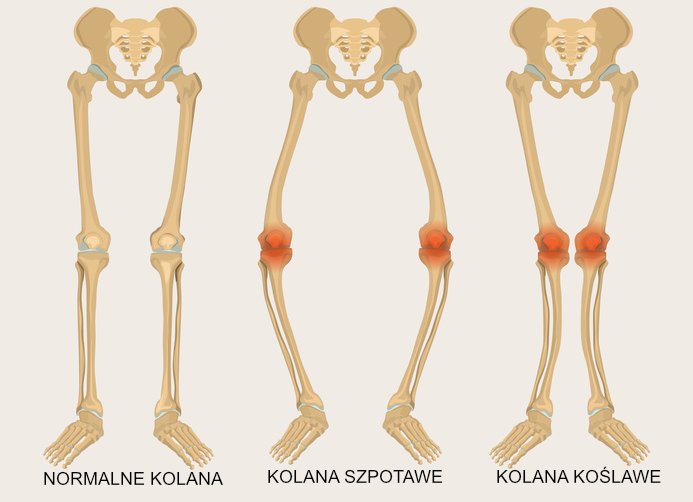

- Deformacje stawów. Zdeformowany staw będzie zużywał się szybciej, podobnie jak opona na źle ustawionym kole samochodu. Dlatego też tak zwane krzywe, czyli koślawe lub szpotawe kolana ulegają degeneracji znacznie szybciej normalnie.